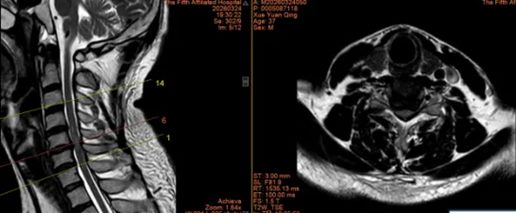

2.山西省晋城市沁水县龙港镇 44岁李女士

640 (2)_副本